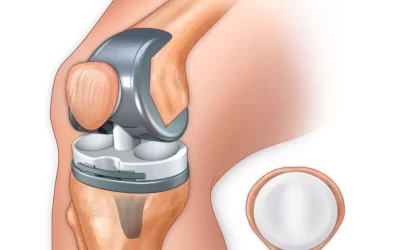

عمل تعویض مفصل زانو یک روش درمانی موثر برای افرادی است که دچار درد شدید، محدودیت حرکتی یا تخریب پیشرفته مفصل هستند. این جراحی به کاهش درد، بهبود حرکت زانو و بازگشت فرد به فعالیتهای روزمره کمک...